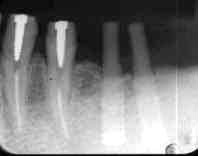

図3.5│術前 1986年11月27日 根管治療+根尖掻爬+HAP 50歳 女性  |

図4.術後1年 1988年1月20日 4│予後不良による再Ope時 5│根尖部では骨再生を確認  |

図5.再手術時 1988年1月13日 前回の手術が成功した5│根尖部では アパタイトを取り込んだ骨の再生が 認められる  |

骨補填材として臨床応用した際の特徴は、親和性に優れ、骨の再生が可能な条件の下ではそれを

阻害しない点である。具体的に例を挙げると、抜歯窩(図1,2)や根管治療後の根尖病巣

(図3〜5)に於いては、アパタイトを取り込んだ骨の再生が認められる。

これは、抜歯或は根管治療により原因が完全に除去され、アパタイトの使用無しでも骨の再生が

可能な状況であると考えられる。

(図6〜8)